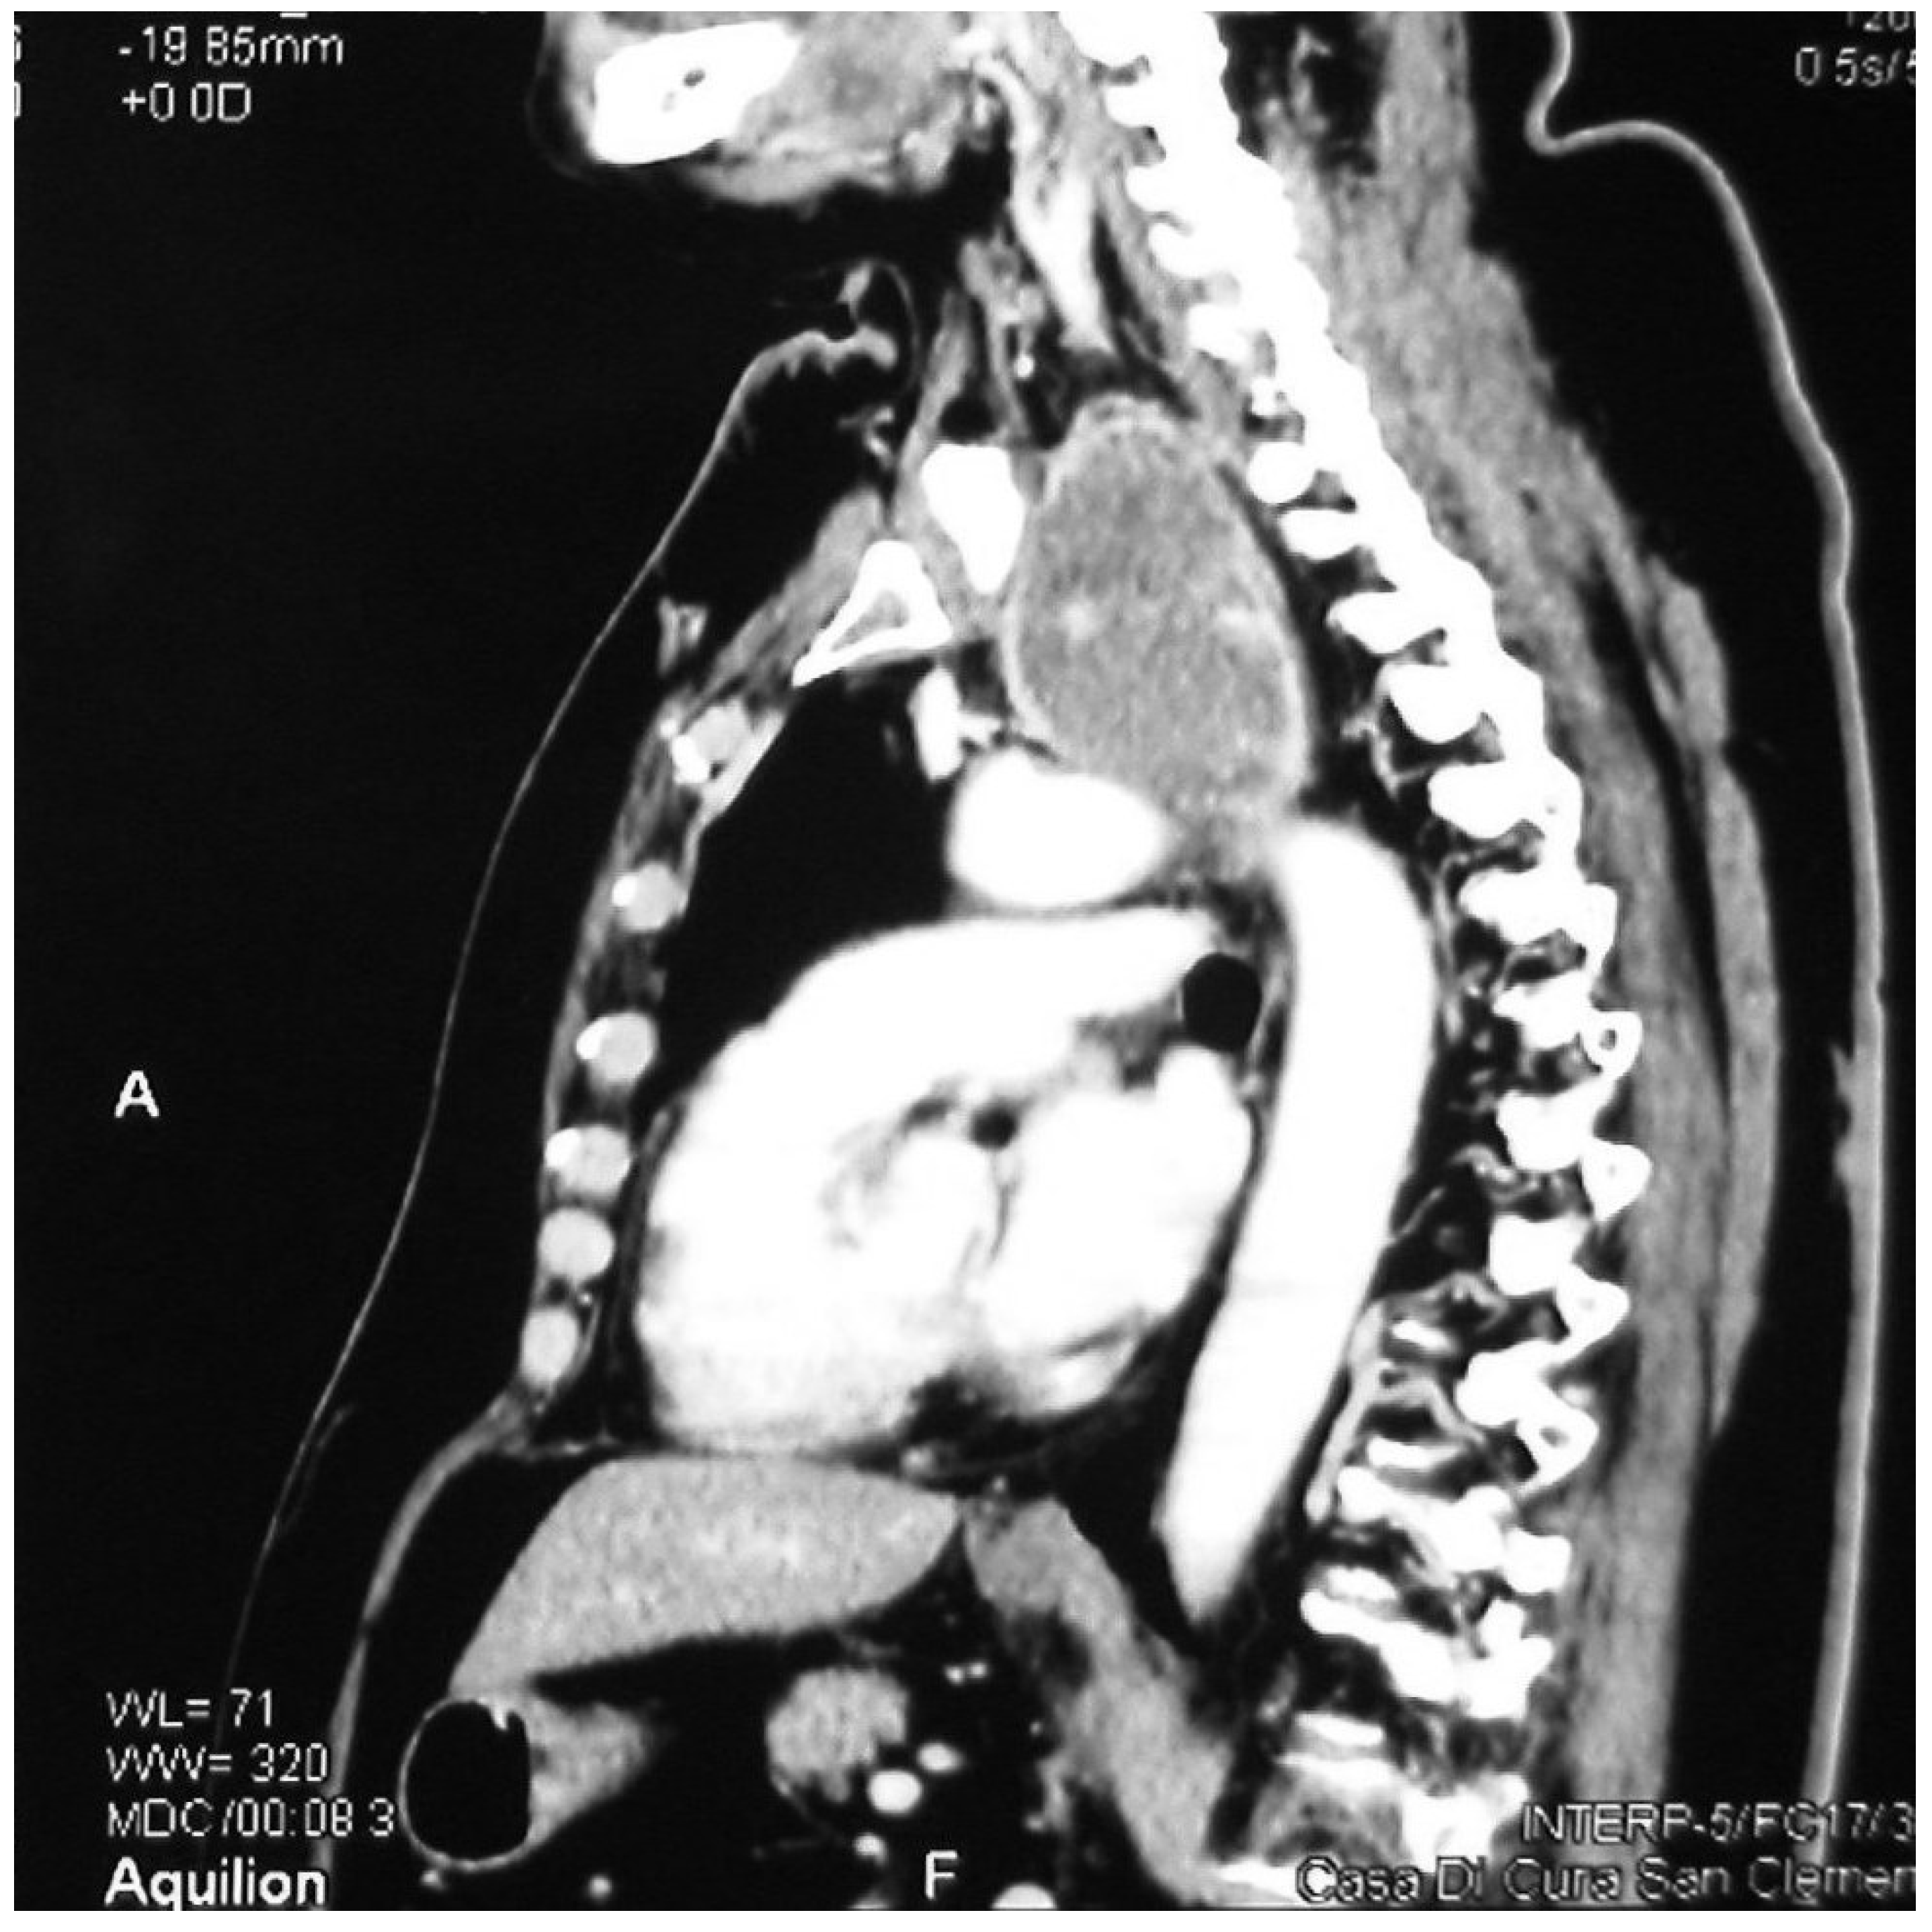

Figure 2.

Sagittal CT showing a retrovascular retrosternal goitre.

A total of 173 cervico-mediastinal goitres (67.6%) resulted from a prevascular localization and 83 (32.4%) were in retrovascular positions (Figure 1 and Figure 2). There were 8 autonomous goitres (3%): 7 prevascular and 1 retrovascular.